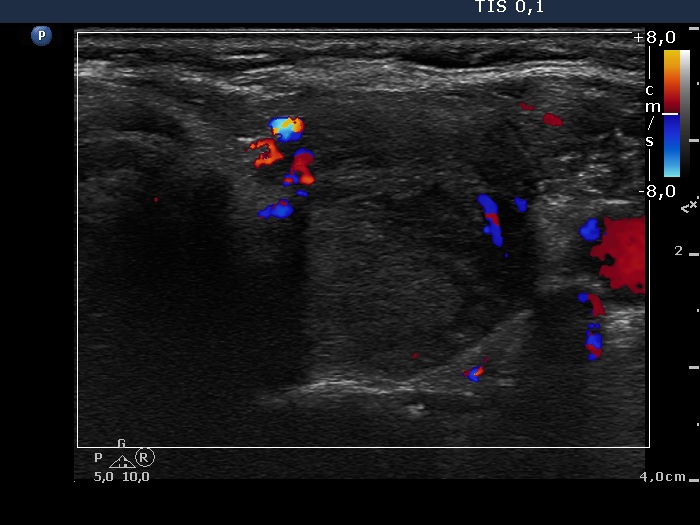

Follow-up examination two years after the first visit (ultrasonographic picture 6)

Left lobe, transverse scan, color Doppler mode. The vascularization of the discrete lesion is not specific.